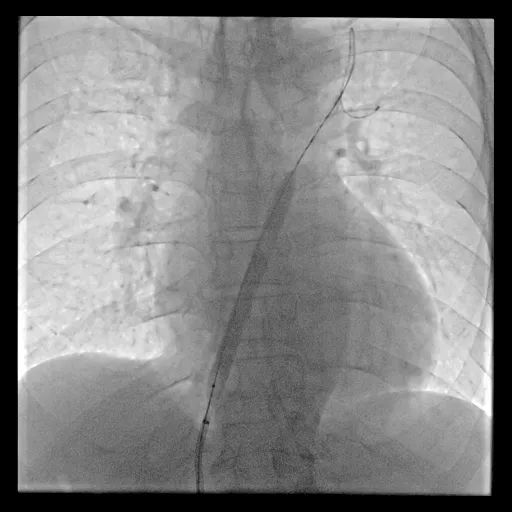

手术过程

球囊扩张房间隔

手术用时1小时15分钟,术中采用10mm球囊预扩张房间隔,并植入8mm孔径心房分流器。术后左心房压力下降,患者胸闷气短症状明显好转,次日患者即可下床活动,术后5天复查各类指标且康复良好,顺利出院。